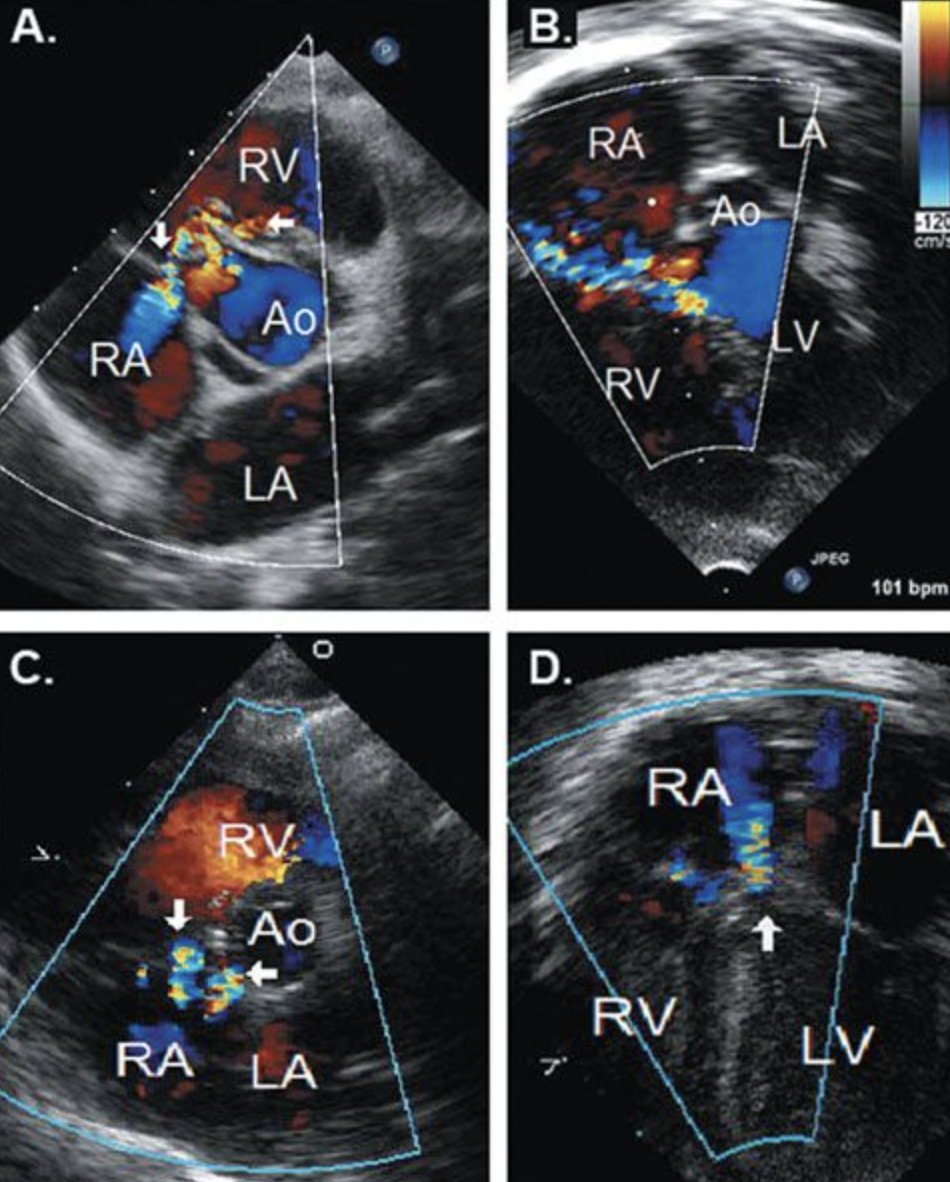

16

Q

What is this? (Be specific)

A

Perimembranous VSD

17

What is this? Be Specific

Muscular VSD

18

Inlet VSD

22

What specific kind of VSD is this?

Gerbode Defect